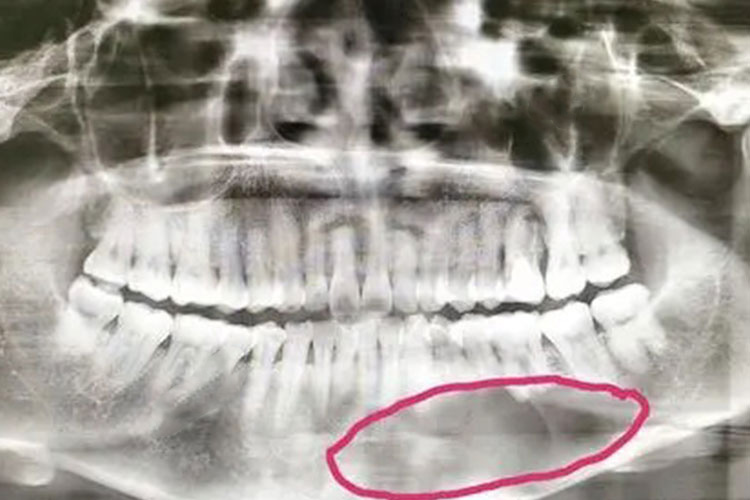

早期牙源性颌骨囊肿诊断较难,依据病程长短,肿物部位,触诊时发生乒乓球感或波动感,X线检查,穿刺及穿刺液涂片显微镜下检查也有助于诊断。非牙源性颌骨囊肿根据囊肿发生部位及牙髓是否存在活力等特征诊断。